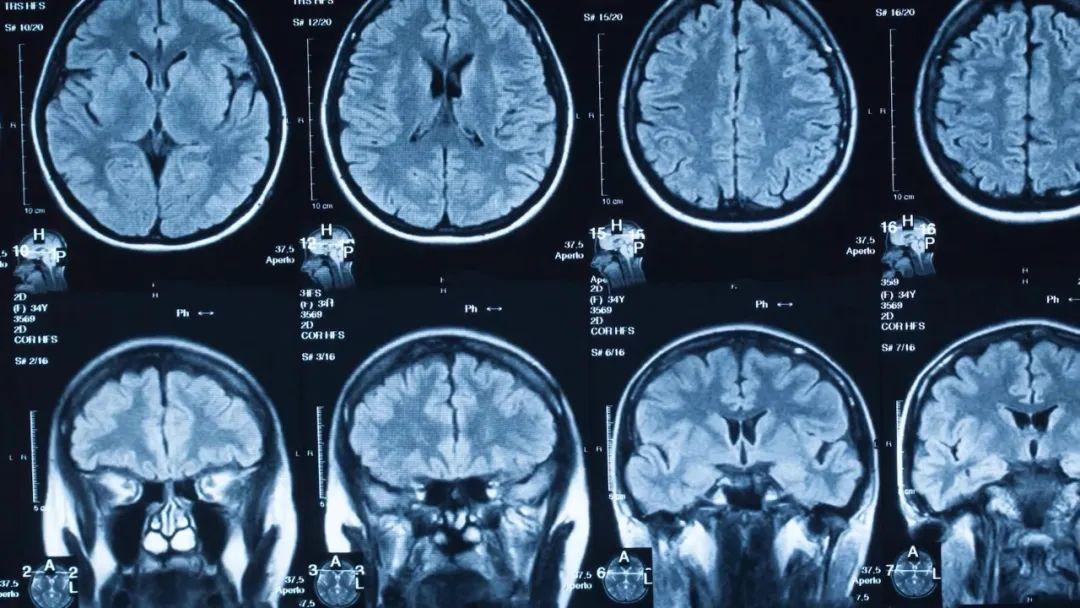

核磁共振成像是医学中应用最广泛的成像方法之一,由于担心人们认为其名称中的“核”与核辐射有关,因此将它重命名为磁共振。事实上,这个“核”与核辐射无关,只是用来描述产生共振的原子核,更准确来说应该是原子核的旋转。

对于人体中的核磁共振成像,通常以氢核为目标,因为其中水和脂肪中有很多,然后图像的亮度基本上可以告诉我们脂肪和水的数量。人们也可以瞄准其它原子核并进行测量,这就导致了不同核磁共振图像的工作方式不同。核磁共振成像非常适合于检查软组织,而对于骨折一般则使用X射线成像。